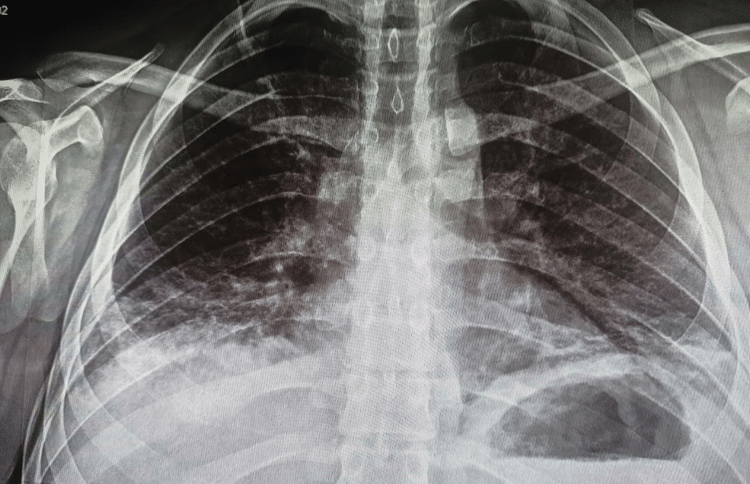

Le solicito una Radiografia y confirmo mi diagnostico. La Radiografia muestra el infiltrado basal pulmonar y pleurits basal derecha, compatible con Neumonía Lipoidea exógena.